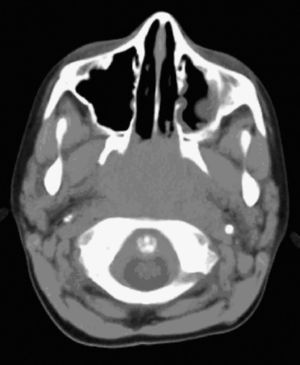

Caso clínicoPaciente de 9 años, varón, sin antecedentes de interés, que consulta en el Servicio de Urgencias por epistaxis. Refiere 10 episodios en los últimos 3 meses, autolimitados, de 10min de duración. Diagnosticado un mes antes de anemia ferropénica en tratamiento. En la exploración destaca una epistaxis activa, palidez mucocutánea, adenopatía laterocervical izquierda de 2×2cm, móvil, de consistencia dura, dolorosa a la palpación, no adherida a planos profundos, sin signos inflamatorios evidentes, controlada por su pediatra, y otras menores de 1cm, submandibulares y cervicales bilaterales. En el resto de la exploración no hubo hallazgos. En Urgencias no se visualiza el punto de hemorragia y se realiza taponamiento anterior. La analítica evidencia anemia ferropénica sin trastornos de la coagulación. Se realiza una tomografía computarizada (TC) maxilofacial, en la que se visualizó una ocupación de la luz del cavum (fig. 1). Se completa el estudio con exploración endoscópica nasal, en la que se visualiza una masa rinofaríngea en pared posterosuperior y se cauteriza con bisturí eléctrico, cediendo la hemorragia. Se toma muestra para biopsia, que da como resultado un carcinoma indiferenciado de cavum (fig. 2). Posteriormente, se envió al paciente al Servicio de Oncología pediátrica para seguimiento y tratamiento con radioterapia.